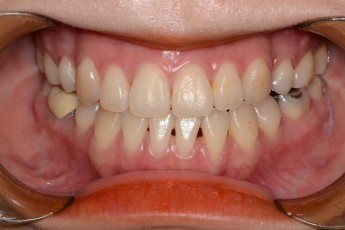

BEFORE & AFTER

- 덧니교정